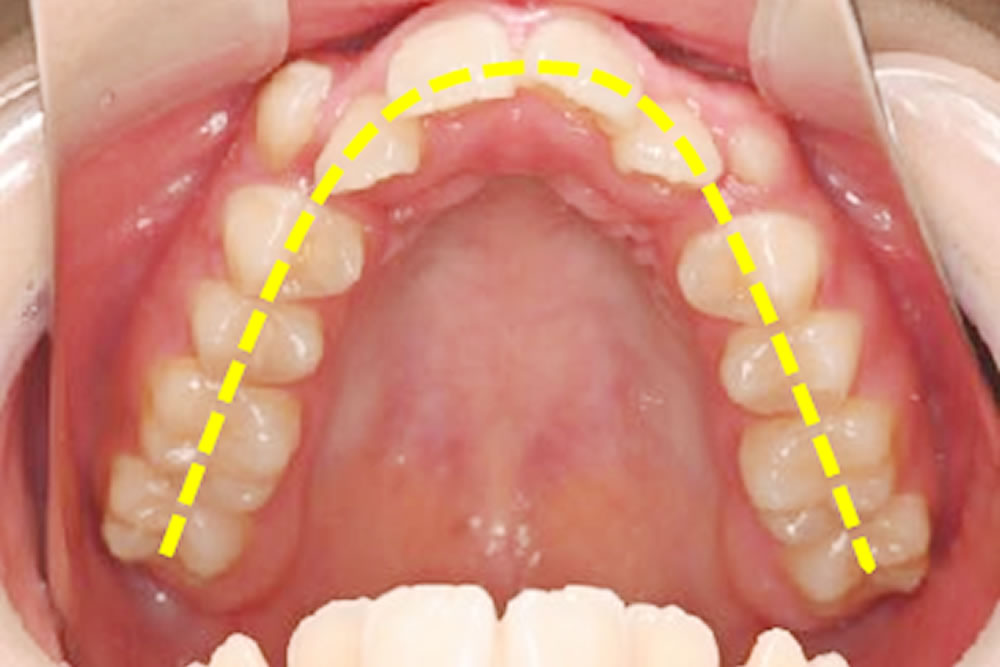

上の犬歯が出ているのと全体的な歯並び、噛み合わせが気になるとの主訴で来院された患者さまです。

CT画像、模型分析、口蓋形態の検査などを行い、患者様の上顎歯列は、歯列だけを広げるのではなく、骨から広げる必要があることが分かりました。

【初診時】